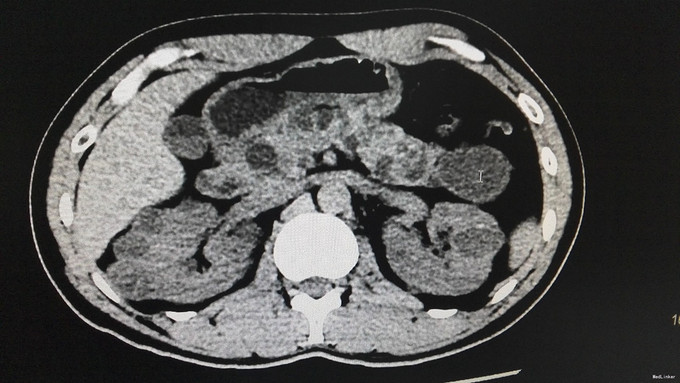

查体:背部后正中线上长7cm手术瘢痕。双肾区无红肿、隆起,左肾区压痛、叩痛,右肾区无压痛、叩痛,左肋脊点、肋腰点压痛,右肋脊点、肋腰点无压痛。左侧上中输尿管点压痛,右侧上中输尿管点无压痛,膀胱区无压痛。辅查:门诊CT示:1、胰腺多发囊肿,双肾多发肾癌,双肾多发囊肿,考虑VHL综合征。2.肝S2/4异常强化灶,考虑异常灌注。家族史:父亲肾癌去世。

诊断:VHL综合征

VHL综合征就是“Von Hippel-Lindau综合征”的简称,即CNS血管母细胞瘤合并肾脏或胰腺囊肿、嗜铬细胞瘤、肾癌以及外皮囊腺瘤等疾病。 VHL综合征是一种罕见的常染色体显性遗传性疾病,疾病是因位于染色体3P25.3的VHL抑癌基因发生突变所致。VHL的临床表现和症状包括血管瘤、血管母细胞瘤、嗜铬细胞瘤、肾细胞癌,胰腺囊肿(胰腺浆液性囊腺瘤)以及咖啡牛奶斑。VHL综合征患者平均寿命不超过49岁。其主要死亡原因是中枢神经系统血管母细胞瘤破裂出血、肾细胞癌和嗜铬细胞引起的恶性高血压。本例患者脊髓血管母细胞瘤,肾脏或胰腺囊肿,肾癌,结合家族史诊断VHL基本明确。 治疗上,中枢神经病变根据部位行手术或X刀、伽玛刀治疗。嗜铬细胞瘤应手术切除。肾细胞癌的治疗与散发性肾细胞癌有所不同,由于前者常为双侧多发,肿瘤生长较慢,转移较晚,故即使为单侧肾癌,也应尽量行保留肾单位的肿瘤切除手术,因为对侧也有在今后发生肾肿瘤的可能。多年临床观察发现,双侧全肾切除会诱发或加快其它部位的VHL肿瘤的生长,主要认为是由于移植术后的免疫抑制治疗和应用透析的结果。VHL综合征胰腺囊肿无恶变倾向,应不予处理。 VHL基因突变的人群携带率估计为3/10万左右,外显率接近100%。其遗传特征为常染色体显性方式,子女有50%机率发病,故对其子女也应严密随访。